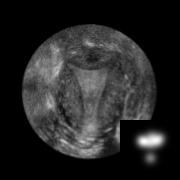

Standard plane (SP) localization is essential in routine clinical ultrasound (US) diagnosis. Compared to 2D US, 3D US can acquire multiple view planes in one scan and provide complete anatomy with the addition of coronal plane. However, manually navigating SPs in 3D US is laborious and biased due to the orientation variability and huge search space. In this study, we introduce a novel reinforcement learning (RL) framework for automatic SP localization in 3D US. Our contribution is three-fold. First, we formulate SP localization in 3D US as a tangent-point-based problem in RL to restructure the action space and significantly reduce the search space. Second, we design an auxiliary task learning strategy to enhance the model's ability to recognize subtle differences crossing Non-SPs and SPs in plane search. Finally, we propose a spatial-anatomical reward to effectively guide learning trajectories by exploiting spatial and anatomical information simultaneously. We explore the efficacy of our approach on localizing four SPs on uterus and fetal brain datasets. The experiments indicate that our approach achieves a high localization accuracy as well as robust performance.